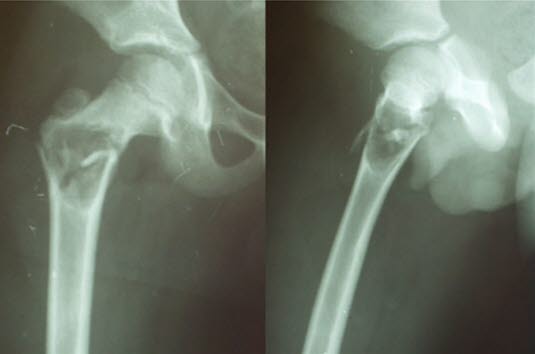

Solitær beincyste i trochanterområdet